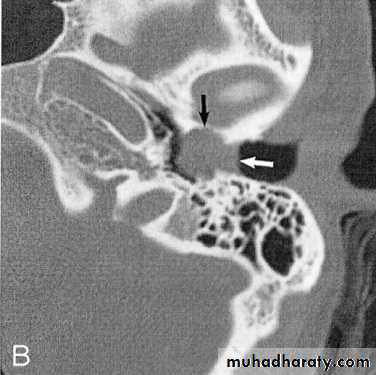

1. Otoscopy: Attic (unsafe perforation) situated in the pars flaccida. Cholesteatoma may be seen as a grayish substance projecting from attic perforations. Granulation tissue may be seen as well occupying such perforation.

2. X-ray and CT scan of cholesteatoma appear as an area of translucency with a clearly outlined bony margin.

Cholesteatoma